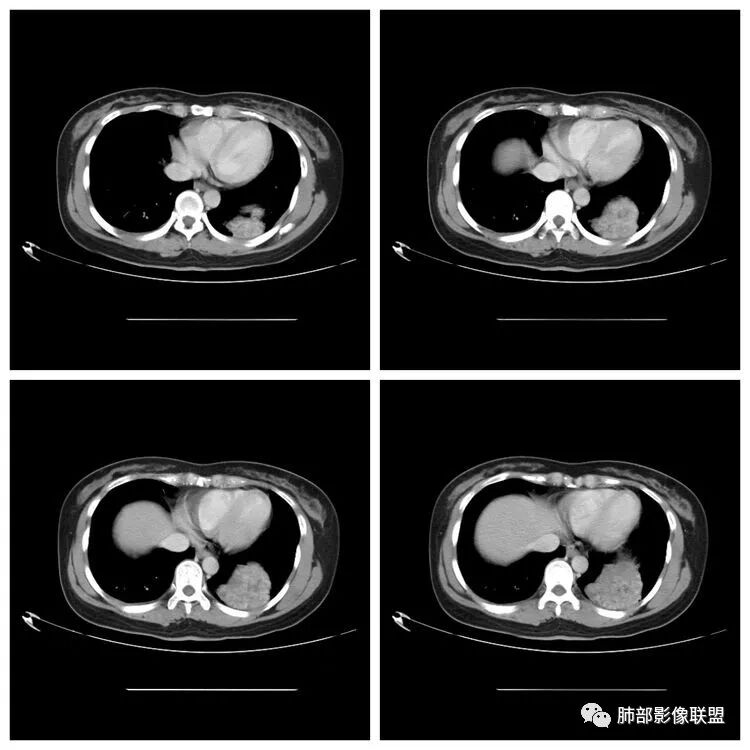

下面看第三部分了,3月20日补增强扫描:

Shelia:尤其体检基本不照侧位片Coke with ice:嗯,很有警示意义的病例。我倾向于定位胸膜来源,SFT?

M-Imaging :错了,这么大,膈肌后方南边:定位?定性?Shelia:肺外。感觉病灶是个扁平状,虽然没有蛇纹血管征,但是延迟强化,怀疑纤维来源,考虑sft

M-Imaging :肿块与胸膜夹角是锐角,有分叶,觉得肺内Lotus:mpr重建再看一下南边:与支气管有关系吗Shelia:没有关系。与胸膜分不清

南边:边缘这么光滑,无分叶,与胸膜关系密切

D字征

首先良性,倾向于SFT,不除外PSP

宇宙星空:延迟明显强化,其内可见条索状低密度,支持SFT

lmg:其内可见血管穿行吧,考虑SFT

一米阳光:与膈胸膜关系密切,肺受压。考虑SFT

脏层胸膜来源孤立性纤维瘤

CT表现:1.多为来自胸膜单发肿块,轮廓较光滑,一般无分叶,可有包膜,可以有胸膜尾征。少数胸膜SFT可表现为带蒂肿块,为本病较为特征性表现。2.当肿瘤较小(小于5cm)时,平扫密度较均匀,为软组织密度,增强扫描呈轻中度均匀强化,少数肿瘤强化较明显。3.随着肿瘤的增大,发生粘液变性、囊变坏死概率增加,多表现为密度不均匀,并可有钙化,增强为轻中度不均匀强化,常表现为“地图样”。

潘军平老师关于定位点评——我们判断肺内肺外的依据:1、与胸膜的关系。主体在外面,宽基底与胸膜连接,胸膜掀起一般是肺外的依据。2.、与肺内结构的关系:附近血管、支气管被推移,未进入病灶(无血供的良性病变有时候要警惕除外),提示肺外。3、血供,肺部来源的一般肺部血供(隔离症除外,恶性肿瘤有时候会有差异,孤立性纤维瘤血供可以肺内来源)。